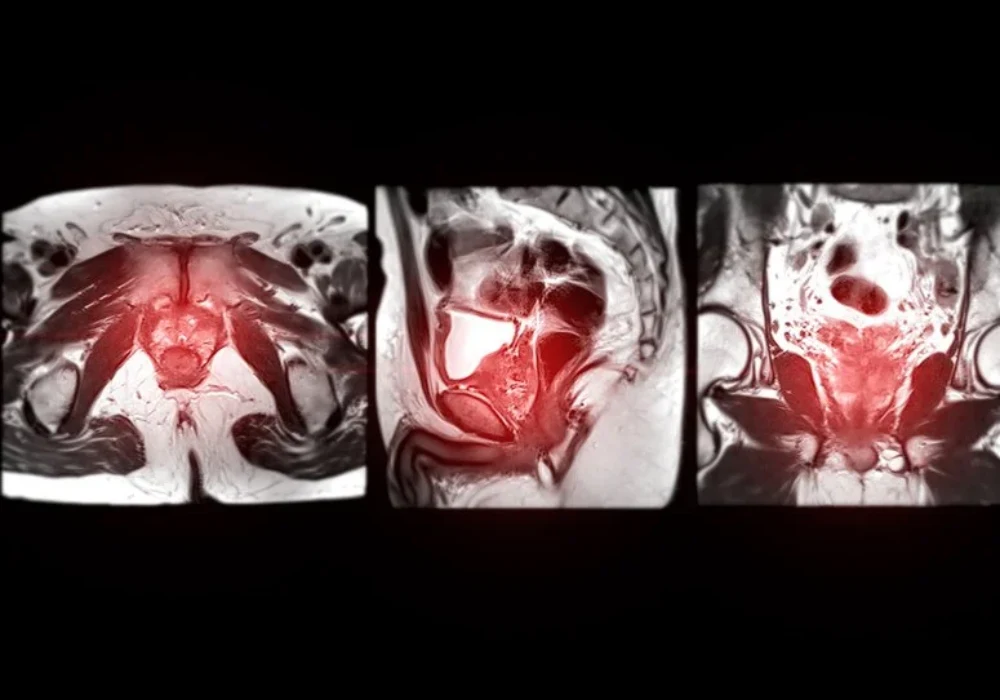

The AI system was a deep-learning segmentation model trained on biparametric MRI inputs, using T2-weighted imaging alongside diffusion information, including a high b-value sequence and an apparent diffusion coefficient map. The dataset was split into a larger training set and a smaller test set. The model produced a case-level likelihood score for clinically significant disease and candidate lesion outputs derived from the predicted probability map.

Performance for clinically significant cancer detection was assessed at the case level using the area under the receiver operating characteristic curve, which was around 0.83 with a confidence interval reported in the source. To understand how this might translate into clinical decisions, specificity was compared at sensitivity levels aligned with common PI-RADS thresholds used by radiologists. Rather than focusing on a single operating point, the analysis matched sensitivity between the AI system and radiologist thresholds, then examined how often each approach correctly identified men without clinically significant cancer.